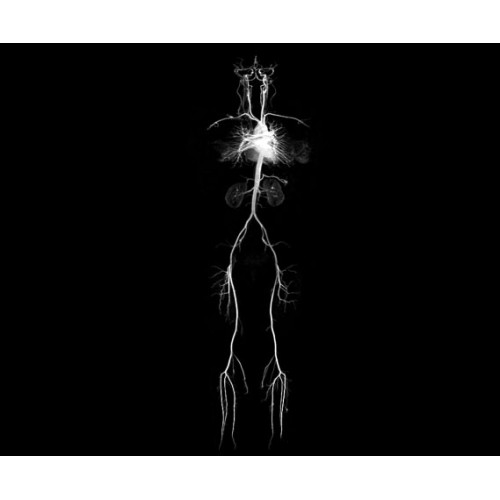

МР-ангиография

Да

Поле обзора 50x50x50 см и апертура шириной 70 см позволят достоверно визуализировать сложные анатомические области для пациентов с крупным телосложением, например, плечи и бедра. Феноменальная однородность системы SIGNA Architect обеспечивает наиболее широкое поле обзора с улучшенными характеристиками градиентов. Ничто не останется незамеченным.

• NeuroWorks — универсальное решение для визуализации анатомии головного мозга, позвоночника, сосудов и периферических нервов с четкой дифференциацией тканей.